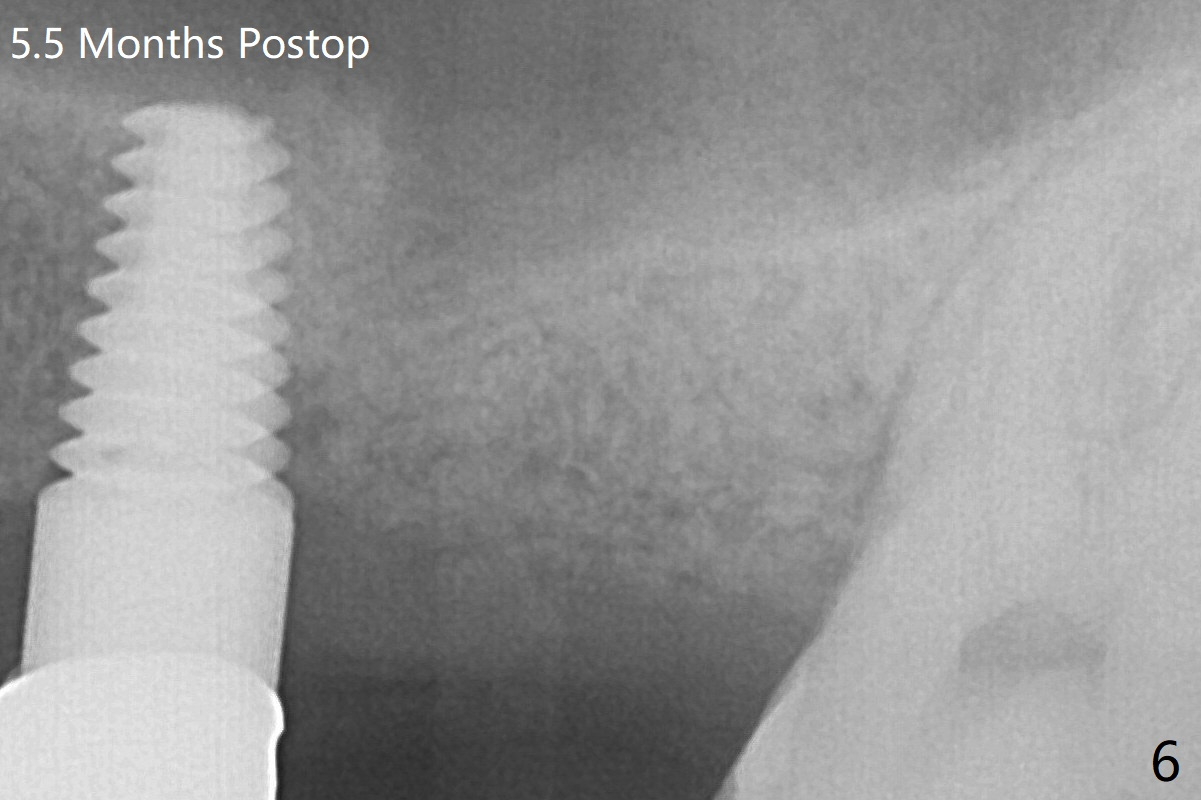

By breaking the proximal contacts, the crown, abutment and implant at #14 are shaken loose using forceps.  Finally the crown breaks off.  Make a slot on the top of the abutment and use a screw bit to turn the abutment/implant counterclockwise.  There is abundant granulation tissue with arterial hemorrhage associated with removal.  The defect involves the distal surface of the implant at #13 and the mesial surface of the tooth #15.  Therefore bone graft is deposited in these surfaces (Fig.4 arrowheads).  The bone height 5.5 months postop should be enough for implantation (Fig.6).